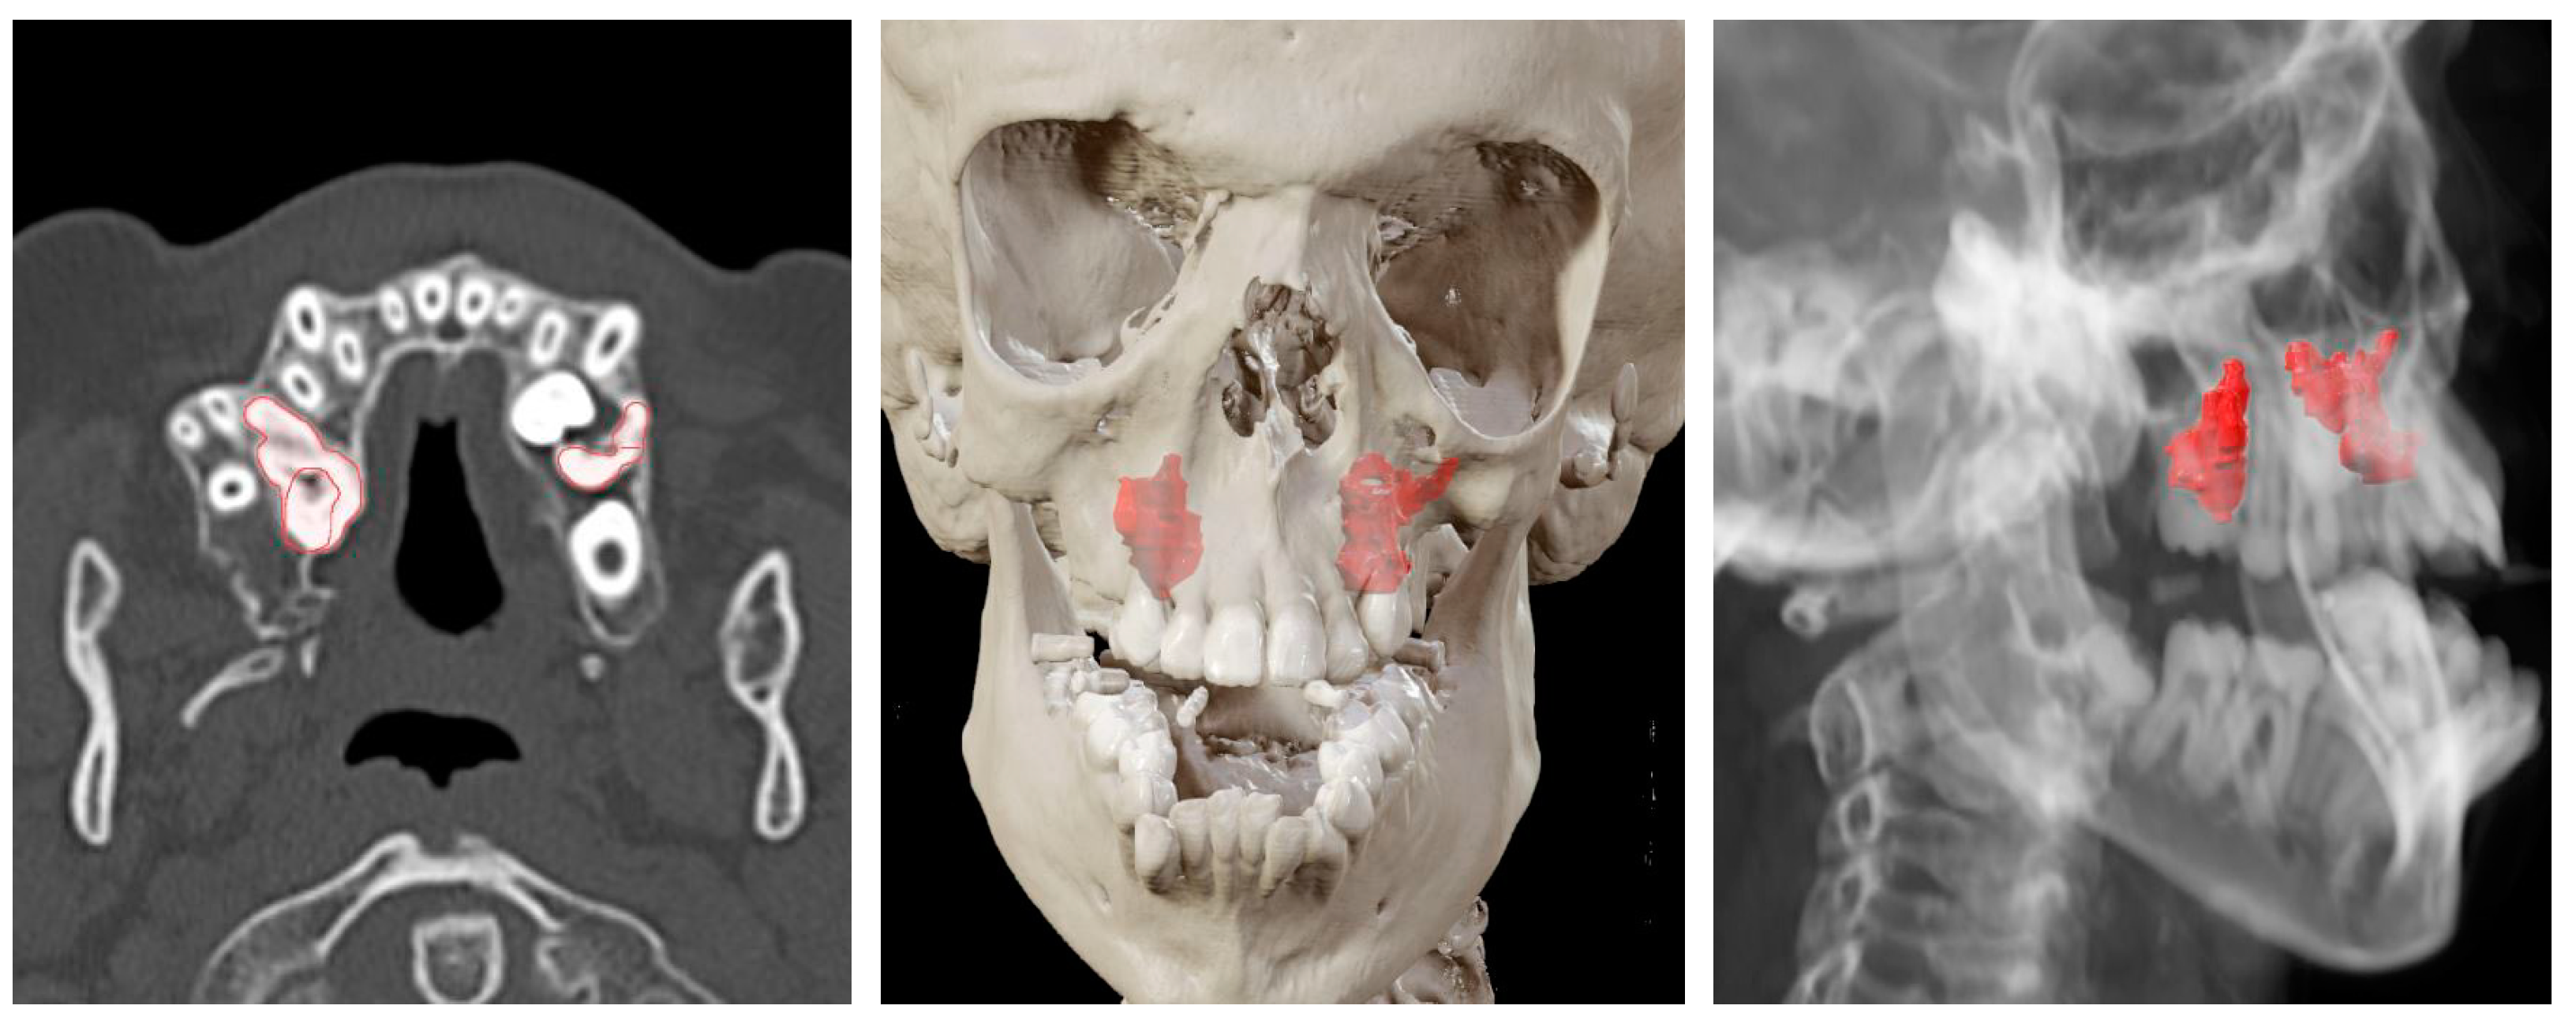

| Case 2 Impacted teeth in Pfeiffer Syndrome | 0.5 mm | 0.3 mm | 0.6 mm | |

| Case 3 Impacted teeth in Apert Syndrome | 0.3 mm | 0.5 mm | 0.4 mm | 0.5 mm |